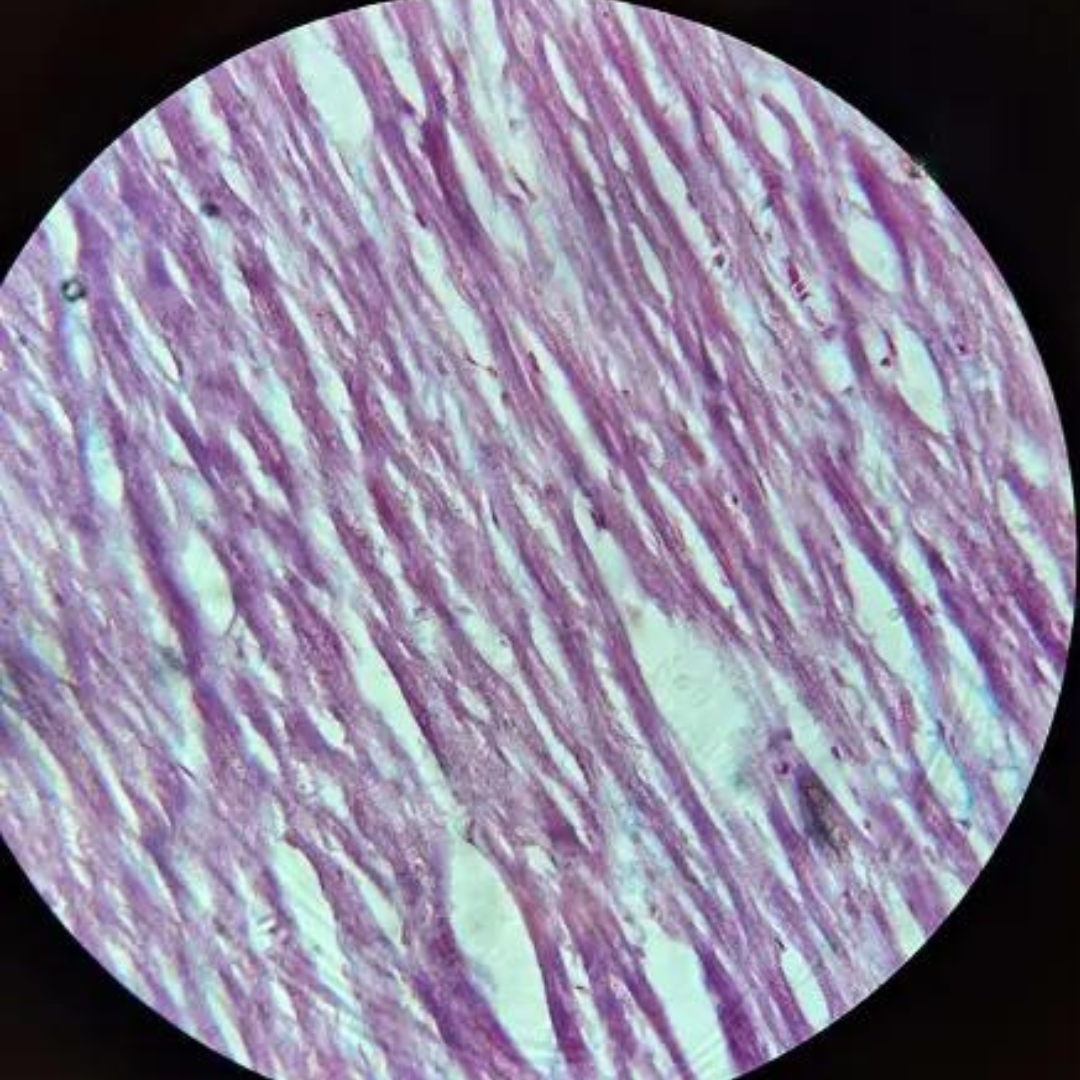

Mucous Tissue